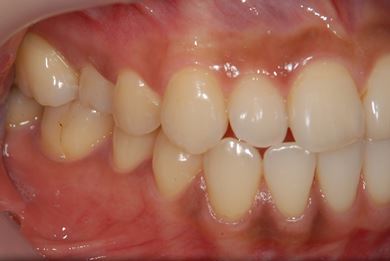

| 性別/年齢 | 女性 / 27歳 | ||||||||||||||||||||||||||||||||

| 主訴 | キャンペーンインプラントを受けたい。 | ||||||||||||||||||||||||||||||||

| 治療方針 | インプラント治療にて、機能的・審美的回復を行う。 | ||||||||||||||||||||||||||||||||

| 治療内容 | インプラント1本、メタルボンドセラミッククラウン1本 | ||||||||||||||||||||||||||||||||